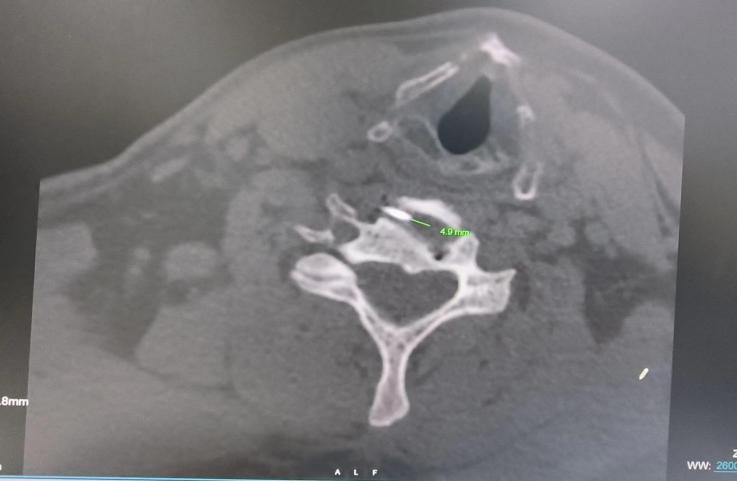

张红主任、孙媛媛医师充分完善术前准备后在CT室姜永宏主任、创伤与老年脊柱科钱立雄副主任医师的协作下,超声引导下避开颈动静脉、神经等重要结构,将穿刺针实时精准穿刺入目标颈椎间盘,CT验证穿刺针针尖位置准确后注药,术中无出血,术后即刻患者头晕、心慌、胸闷等症状明显缓解,责任椎间盘明确,为临床术前精准诊断提供有力依据。

CT验证穿刺针针尖位置准确,注药